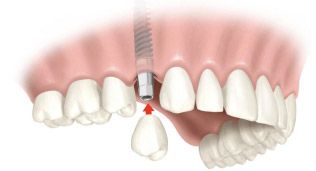

Протезирование - установка коронки на имплантат

Финальный этап восстановления зубного ряда, крепление коронковой части зуба к вросшему в костную ткань титановому основанию - имплантату.

При протезировании на имплантатах модель челюсти и конкретного зуба, и моста и всей челюсти строится в программах 3D проектирования. Они позволяют точно рассчитать высоту и ширину коронки и длину абатмента, основания соединяющего коронку с имплантом.

Коронки и абатменты изготавливаются индивидуально, по 3D модели челюсти пациента.

3D моделирование и точность фрезерного оборудования позволяет создавать конструкции которые сразу идеально устанавливаются и не меняют привычный прикус пациента, что нередко происходит при установке металлокерамических коронок изготовленных методом литья.